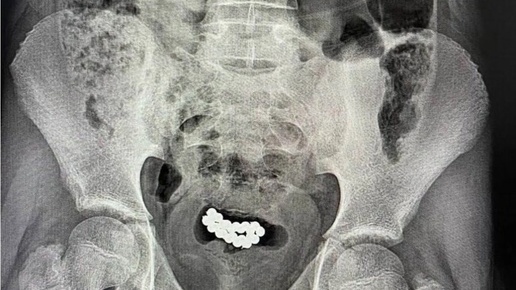

Вот вам свежая порция новостей с полей научного прогресса, где поколение так называемых замеров, снова впереди планеты всей. На этот раз местом для прорывных изысканий стал славный город Саратов. Двое юных естествоиспытателей, 15 и 16 лет от роду, видимо, сочли школьный курс физики недостаточно наглядным и решили дополнить его своей исследовательской работой. Темой их изысканий стало взаимодействие магнитных полей и… некоторых интимных аспектов мужской физиологии. Объектом исследования выступили 80 магнитных шариков – мелочь, а приятно, как подумали наши ньютоны...